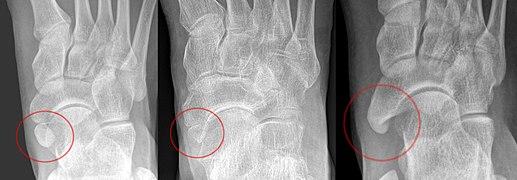

The Geist classification divides the accessory navicular bones into three types.[3]

• Type 1: An os tibiale externum is a 2–3 mm sesamoid bone in the distal posterior tibialis tendon. Usually asymptomatic.

• Type 2: Triangular or heart-shaped ossicle measuring up to 12 mm, which represents a secondary ossification center connected to the navicular tuberosity by a 1–2 mm layer of fibrocartilage or hyaline cartilage. Portions of the posterior tibialis tendon sometimes insert onto the accessory ossicle, which can cause dysfunction, and therefore, symptoms.

• Type 3: A cornuate navicular bone represents an enlarged navicular tuberosity, which may represent a fused Type 2 accessory bone. Occasionally symptomatic due to bunion formation.

Radiological images